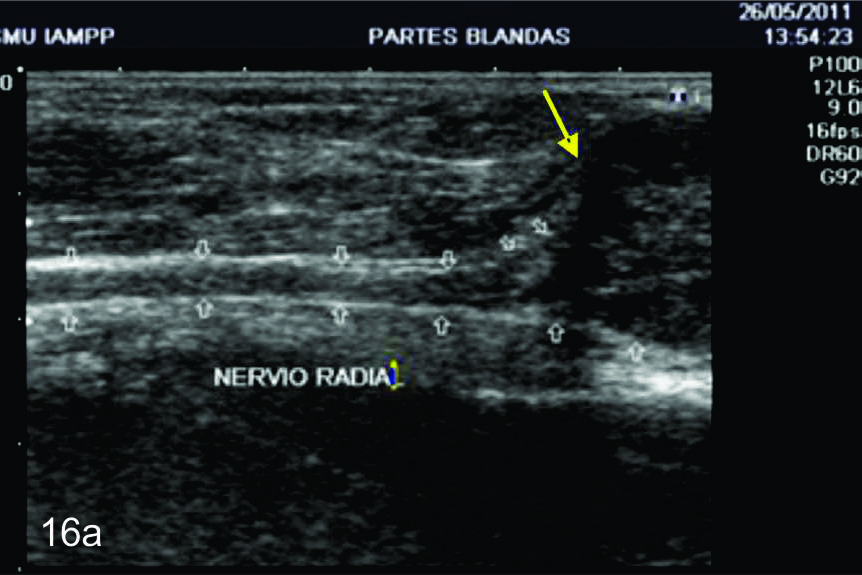

Figura 16

Tumor del nervio radial a nivel del brazo derecho.

A- Se observa un corte longitudinal del nervio radial proximal a la lesión (flechas blancas abiertas), se observa como el mismo se encuentra levemente engrosado y como se continúa con la masa en estudio (flecha amarilla). B- Corte transversal del mismo paciente en donde se identifica un tumor homogéneo ligeramente hipoecogénico y bien delimitado de los planos musculares adyacentes (flechas blancas abiertas).